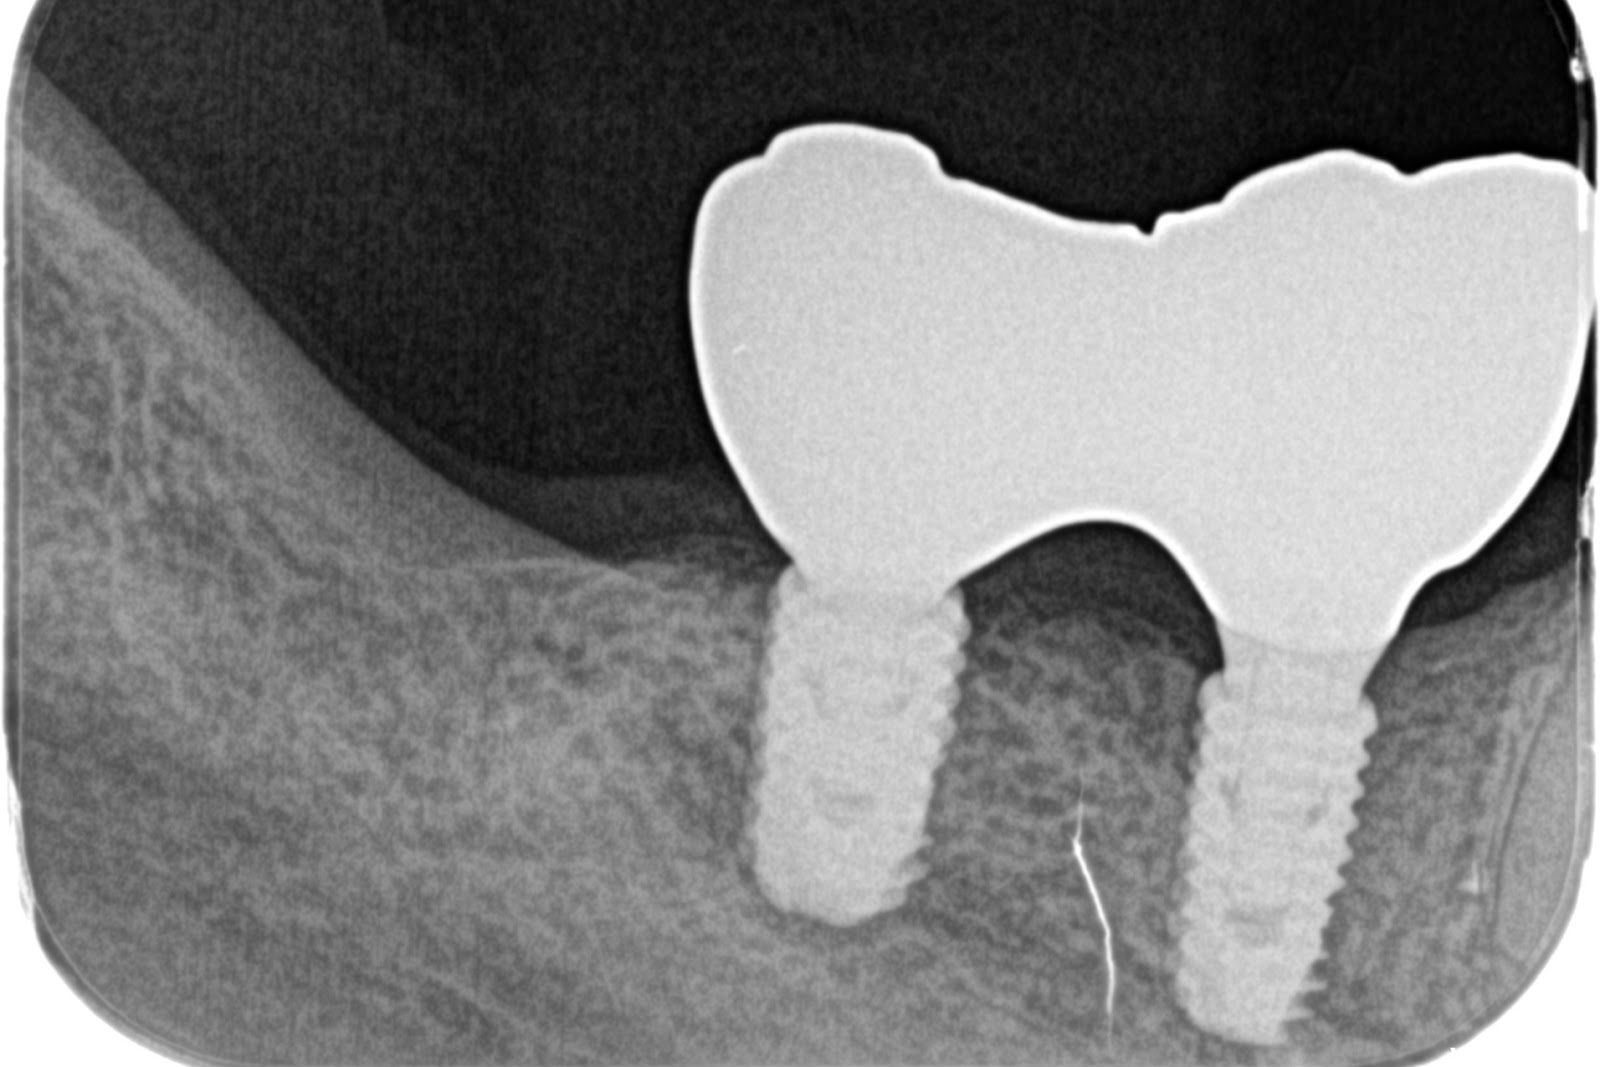

インプラント埋入

50代 女性

40代 女性

20代 男性

60代 男性